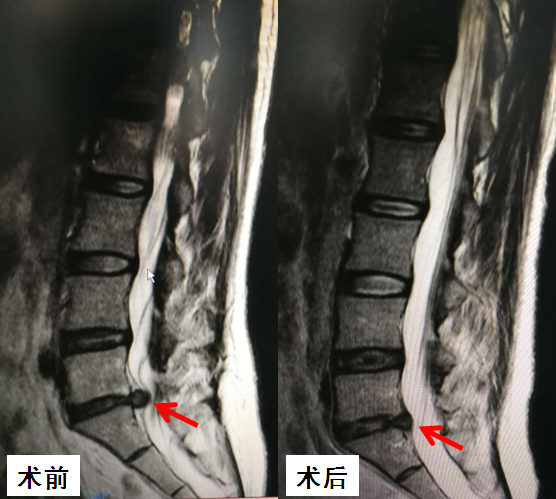

近日,患有腰椎间盘突出症的马女士在我院脊柱骨关节病科体验了一次轻松愉快的手术方式——微创椎间孔镜手术,术后腰腿疼痛症状即刻缓解,病灶清除。这是广西首例采用椎间孔镜结合钬激光微创治疗腰椎间盘突出症,该手术的成功实施标志着市人民医院脊柱微创手术方面已达国内先进水平。

到我院脊柱骨关节病科就诊时,诊断为腰5骶1椎间盘突出症。“按照传统腰椎间盘突出症的手术治疗方案,该患者需要接受开放手术治疗。”脊柱骨关节病科主任吴显培说:“但传统的开刀手术需要全身麻醉,相对创伤较大,康复慢。患者也因为害怕开刀不肯接受手术。”

吴显培决定为其进行目前最先进的微创椎间孔镜手术,只需要局麻即可完成,手术切口仅1cm,手术过程中患者可以玩手机、可以刷微信微博,约60分钟谈笑间手术就顺利完成了,全程几乎无出血。手术当天马女士就能下地行走,3天后顺利出院。